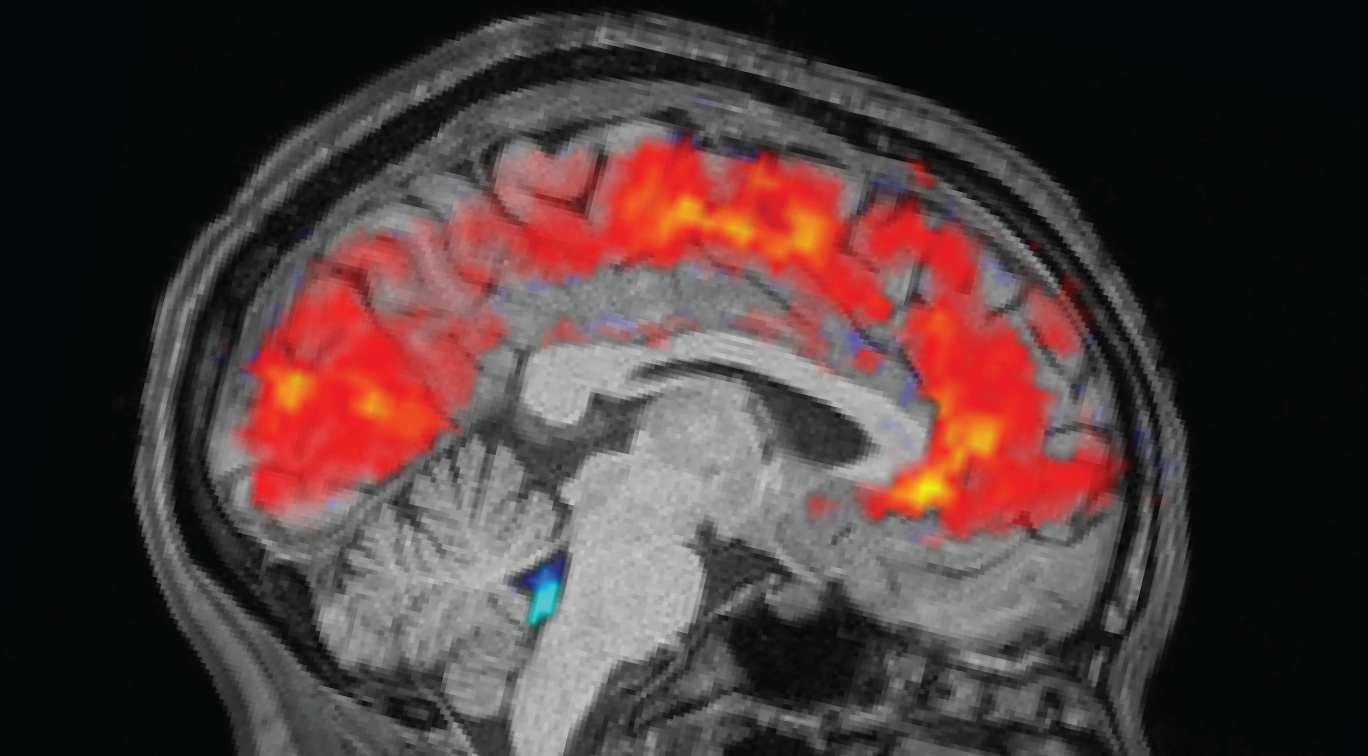

Scientists spot brains zoning out in real time

Ever get that feeling — say, at the end of the week — when you really want to pay attention to something important, but you just zone out and see people’s lips moving?

Well, scientists finally have a physiological explanation for why this happens when you’re sleep-deprived: Your brain is literally flushing out cerebrospinal fluid, making it nigh-impossible for you to concentrate. The exact functional reason for this is still unclear, but scientists think it could have something to do with sleep-deprived brains switching into sleep-like states, possibly as a form of waking brain waste disposal you missed out on the night before.